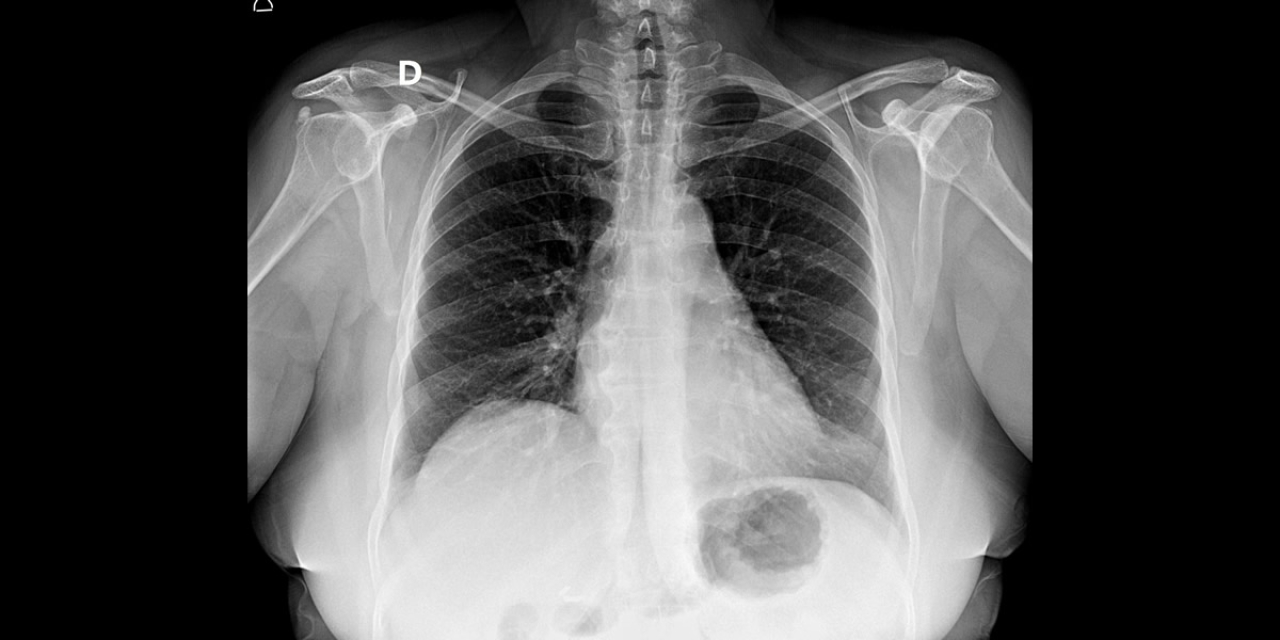

A Prefeitura de Bebedouro, através da Secretaria Municipal de Saúde (SMS), avança na modernização do serviço de diagnóstico por imagem, com a transição do sistema analógico para o digital.

Essa evolução garante mais qualidade, agilidade e segurança no atendimento aos pacientes, além de representar economia de recursos públicos, com a redução de custos operacionais e maior eficiência nos processos.

Com a implantação do novo sistema, os exames e laudos passam a ser disponibilizados por meio de links seguros, facilitando o acesso rápido às informações. Além disso, todo o material ficará integrado ao prontuário eletrônico, disponível em toda a rede municipal de saúde, promovendo a continuidade do cuidado, maior precisão diagnóstica e melhor acompanhamento dos pacientes.